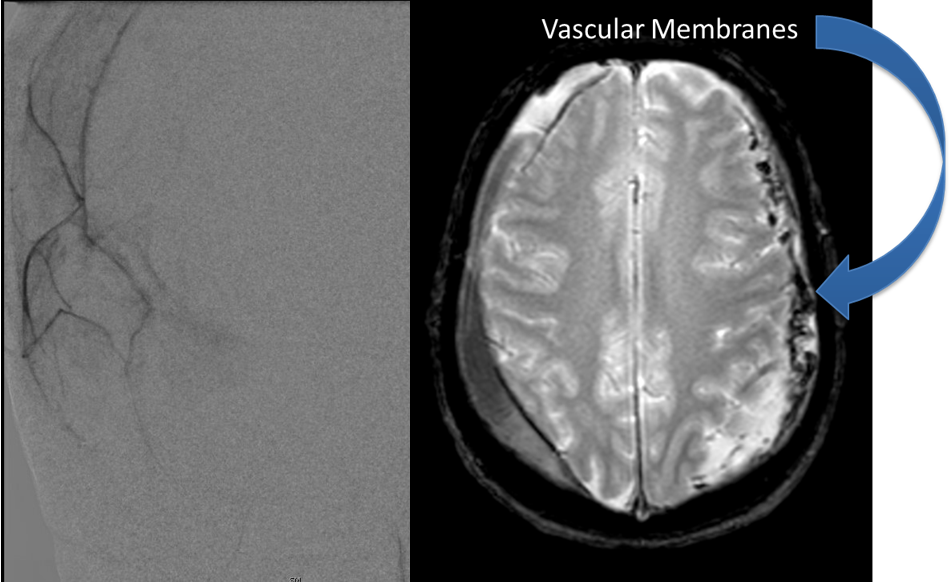

July 22, 2022

Case Presentation: A woman in her 80s developed mild dizziness and headache following incidental trauma working in her garage one day. She presented several weeks later […]